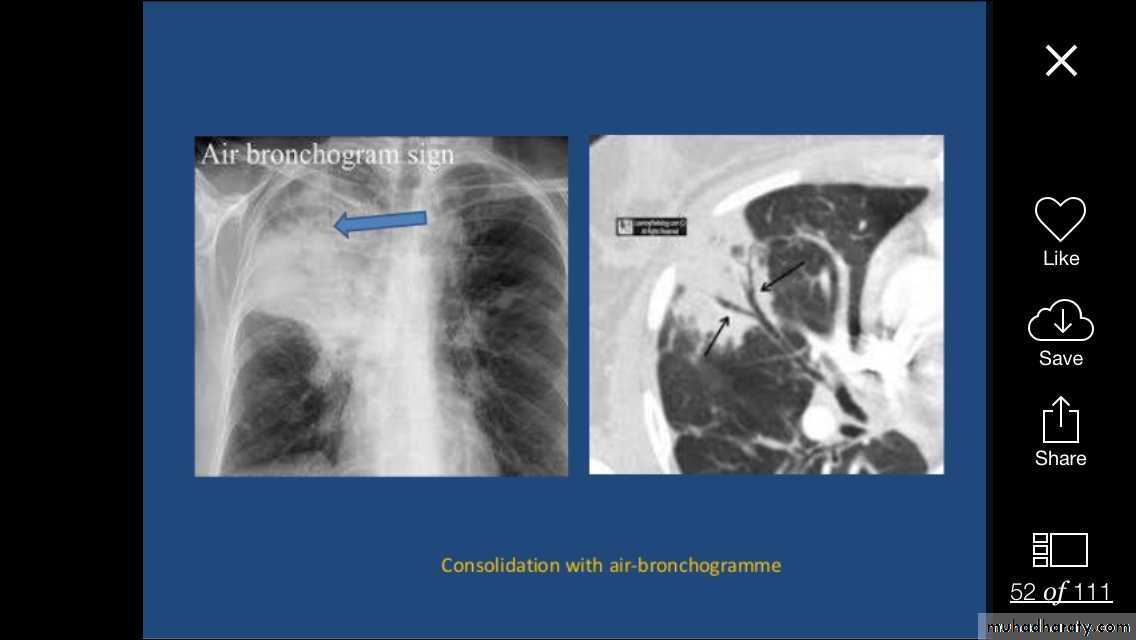

Alveolar shadow (consolidation )

Replacement of air in the alveoli by fluidContain (air bronchogram )

Pneumonia

Pulmunary edemaContusion